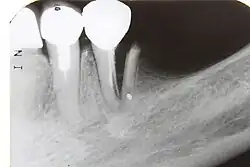

7) Root fracture | Mobile or displaced crown segment

Tender tooth that may be bleeding from the gum Tooth may be discoloured (red or grey) |

Fracture line involving the root will be seen as well as the direction | If displaced, reposition tooth and check the position with an x-ray

Flexible splint used to stabilise tooth for at least 4 weeks and then reassess tooth stability Monitor healing for at least 1 year to assess the status of the pulp Root canal treatment will be needed if pulp necrosis develops (this occurs in ~20% of root fractures) |